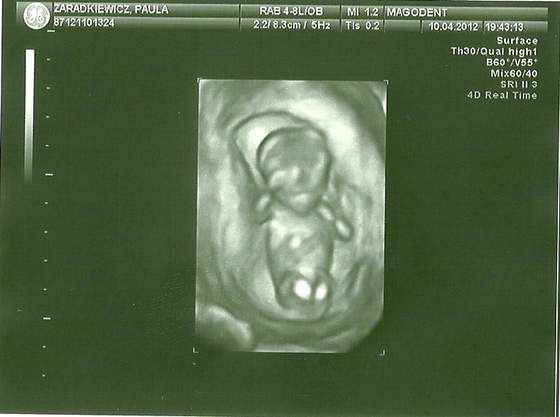

Byłam w poniedziałek na USG 4D (mama zafundowała, bo przecież inaczej to nie poszłabym w życiu :/ )

Cudowna sprawa.

Maluszek szaleje po brzuszku jak nie wiem

Zupełnie co innego jak zwykłe USG.

Zobacz załącznik 455326

Jak tylko na Youtube wrzucę filmik, to podam linka jak szaleje nasze maleństwo w brzuszku :-)